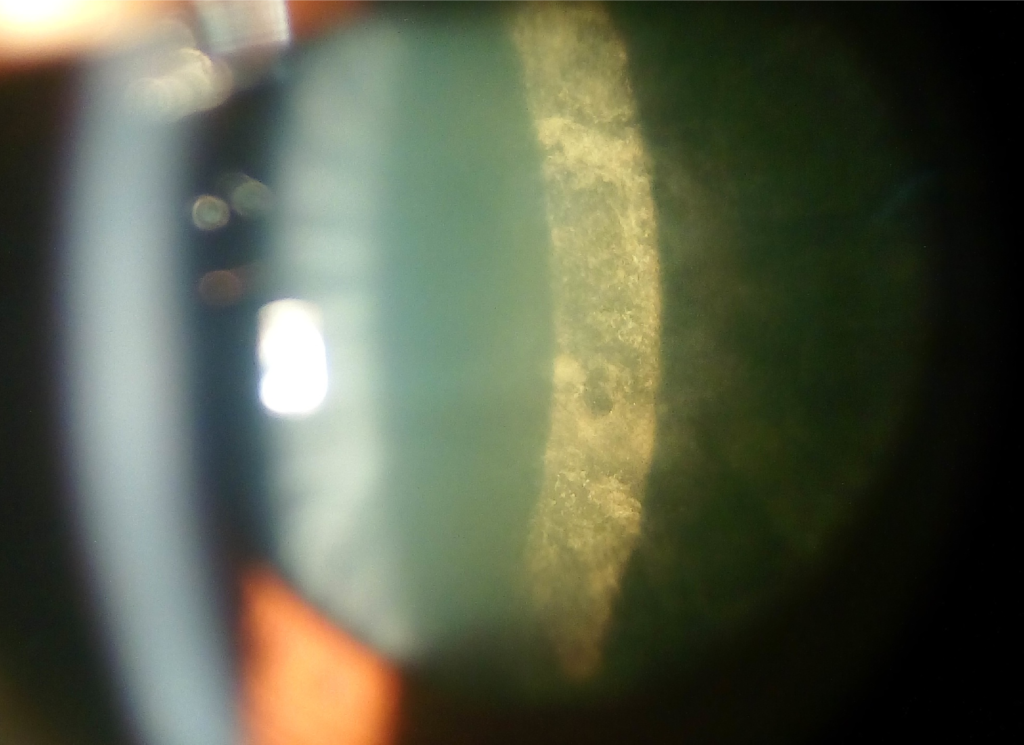

Cataract Causes Blindness . A cataract is a disease of the eye in which the normally clear lens has pacified, which obscures the passage of light. The rate of vision loss can vary depending on different factors. You may have trouble reading or doing other. At first, you may not notice that you have a cataract. Most cataracts develop slowly and don't disturb eyesight early on. More than half of all americans have cataracts by the time they. At first, stronger lighting and eyeglasses can help deal with cataracts. It is a gradually progressive disease and a significant. Cataracts are a leading cause of blindness across the world. But with time, cataracts will eventually affect vision. But certain cataract types can cause vision loss to happen. Cataracts are a leading cause of blindness among older adults in the united states. But over time, cataracts can make your vision blurry, hazy, or less colorful. Yes — if left untreated, cataracts cause continual loss of vision, eventually leading to legal blindness or even total blindness.